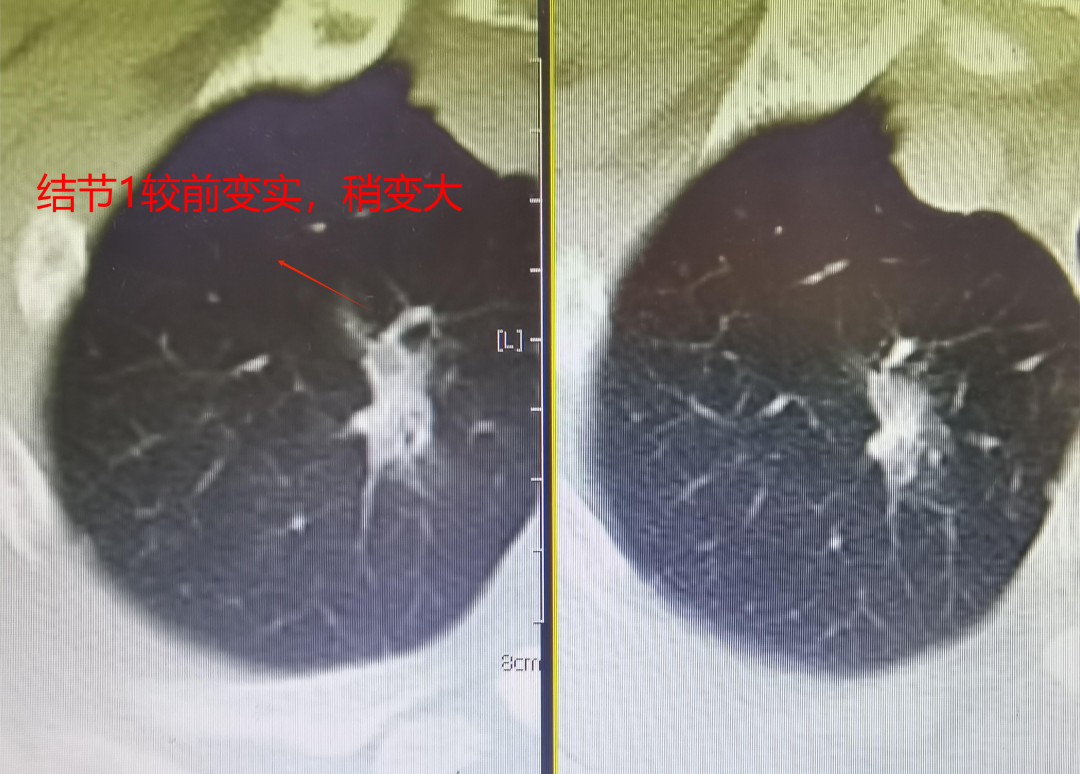

黃大爺5年前經(jīng)我院確診并行賁門癌手術(shù),手術(shù)順利。當(dāng)時(shí),手術(shù)前檢查就發(fā)現(xiàn)了右上肺及右下肺均有一例小結(jié)節(jié),影像檢查排除癌轉(zhuǎn)移,囑患者定期隨訪。今年,接受胸部CT檢查時(shí)發(fā)現(xiàn)兩枚結(jié)節(jié)均較2年前明顯增大、變實(shí),右上肺結(jié)節(jié)約1.2×1.9cm、右下肺結(jié)節(jié)約1.1×1.7cm,影像學(xué)表現(xiàn)高度考慮惡性。

CT影像對(duì)比